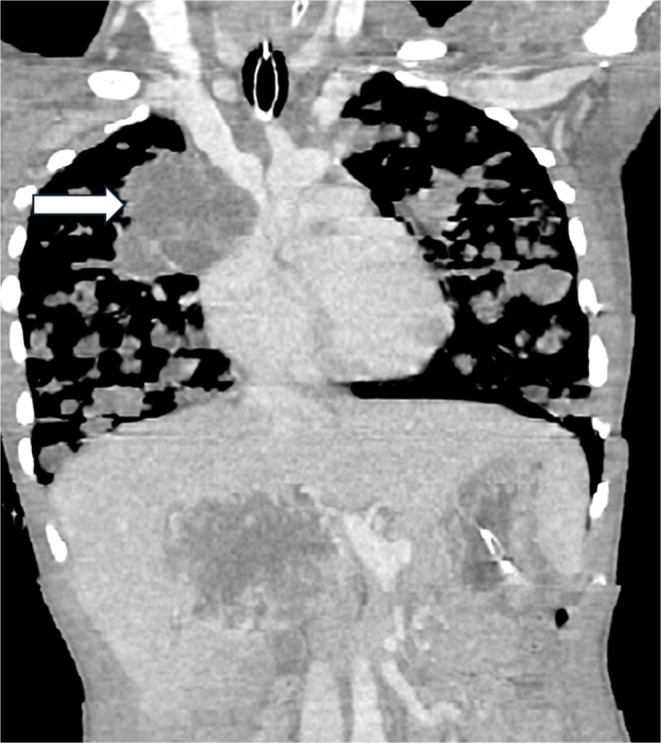

A previously healthy teenager presented with acute respiratory distress and constitutional symptoms. Imaging revealed a mediastinal mass with multiple pulmonary nodules, and markedly elevated β-HCG confirmed metastatic choriocarcinoma. Despite urgent chemotherapy, he succumbed within a week. This case underscores its rarity, diagnostic challenge, and dismal prognosis in tuberculosis-endemic regions.

Abstract Image